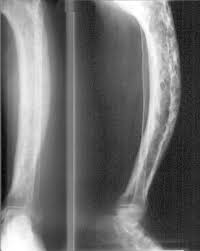

Skeletal System

The Skeletal System is made up of 206 bones in an adult. The functions it performs are; support, movement, protection. The physiology functions are blood cell formation and storage of calcium. There's two basic types of bones: compact bone and spongy bone. This system is the bones and the tissues such as cartilage,tendons, and ligaments that connect to them. The Skeletal System supports the body because without bones our bodies would just collapse on the floor. Also it protects the internal organs, for example the skull protects the brain and the ribs protect the heart and lungs. Last but not least it helps with movement, bones provide the structure for muscles to attach so that our bodies are able to move.